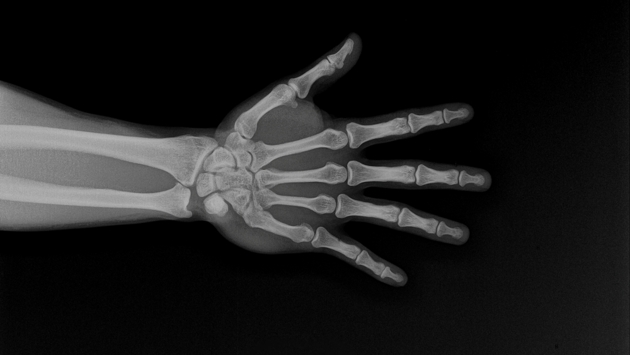

Микропластик обнаружен в человеческих костях — и он их ослабляет

Микропластик находят не только в океанах и на пляжах. Эти крошечные частицы обнаруживаются и внутри человеческого тела, включая мозг, сперму, легкие и кровеносные сосуды. Пластик попадает в организм через воздух, воду и пищу. Шины, текстиль, упаковка и выброшенные предметы — все это вносит мельчайшие частицы в воздух, почву и воду. Мелкие частицы могут перемещаться с кровотоком и оседать в тканях. Новые исследования показывают, как микропластик могут влиять на здоровье костей и костного мозга. Исследователи из Бразилии, Канады и Франции провели метаанализ 62 исследований, чтобы объяснить воздействия микропластика на костную ткань. Работа вышла в Osteoporosis International.

При этом средний уровень отложения микропластика в костях составляет десятки частиц на грамм.

Исследование описывает изменения в поведении клеток, важные для прочности костей. Сигналы, которые способствуют созреванию клеток, оказались ослаблены, в то время как сигналы, способствующие разрушению костей, — наоборот.

В некоторых моделях баланс склоняется в пользу остеокластов — клеток, которые удаляют старую кость. Слишком интенсивное удаление, называемое резорбцией кости, со временем делает скелет более хрупким.

Исследователи также сообщают, что микропластик может проникать в более глубокие отделы костей, включая костный мозг. Нарушение работы костномозгового аппарата может негативно сказаться как на формировании кровяных клеток, так и на обновлении костей.

Возраст и гормональные изменения уже ведут к потере костной массы. Дополнительный стресс от микропластика может усугубить проблему, особенно у людей с другими факторами риска. Международный фонд остеопороза прогнозирует, что число переломов тазобедренного сустава почти удвоится к 2050 году по сравнению с 2018.